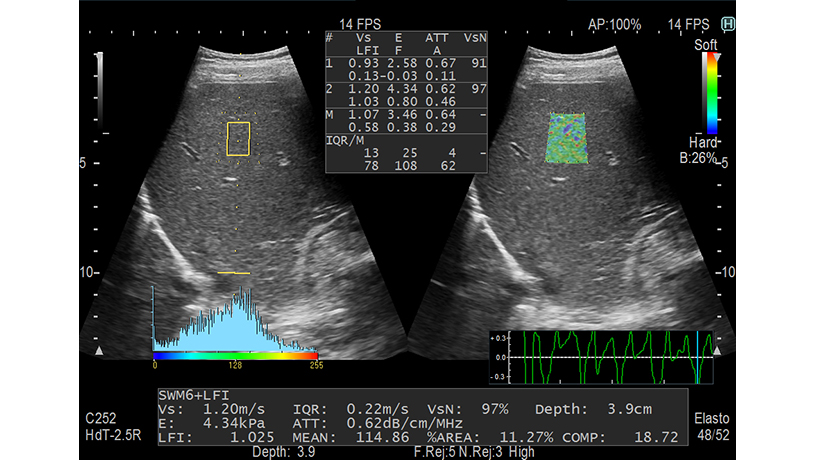

Es posible evaluar la rigidez del tejido mediante la generación de ondas de elasticidad y la medición de Vs, su velocidad de propagación en el tejido. Se espera que Combi-Elasto, que integró RTE y SWM, se utilice para casos que son difíciles de diagnosticar mediante el uso de SWM únicamente.

Función para medir el coeficiente de atenuación generado en el proceso de propagación por ultrasonido del tejido. El grado de esteatosis puede estimarse a partir del tamaño del coeficiente. Su medición se realiza simultáneamente con SWM y puede realizarse como una extensión del examen del modo B.